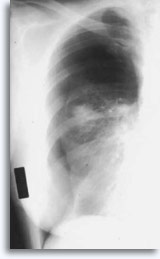

Met transthoracale percutane longaspiratie als referentiepunt, worden bloedingen verwacht als de naald door het borstvlies gaat en het longcelweefsel binnendringt. Dit is gewoonlijk zichtbaar als een versterking van de target in postpunctie borstkasfilmpjes.

Dit wordt soms in verband gebracht met zelf elimiteerde hemoptyse als een klinische reactie van de intraparenchymale lekkage. Pneumothoraxis een bijkomstig verschijnsel van tranthoracale aspiratiebiopsie omdat de naald het borstvlies beschadigt, terwijl deze zijn weg zoekt naar het parenchymatische doel, hetgeen kan resulteren in enige longcollaps. Dit is symptomatisch voor pneumothorax, hetgeen wordt beschouwd als een complicatie. In het algemeen moet er een buis in de borst worden ingebracht zodat de long weer met lucht kan worden gevuld.

Enkele factoren die het voorkomen van symptomatische pneumothorax beïnvloeden, zijn de leeftijd van de patiënt, de afmeting, plaats en diepte van de laesies, het aantal puncties, aanwezigheid van emfyseem, intensiteit van nauwkeurig onderzoek met postprocedurele films en de ervaring van de aspirator.